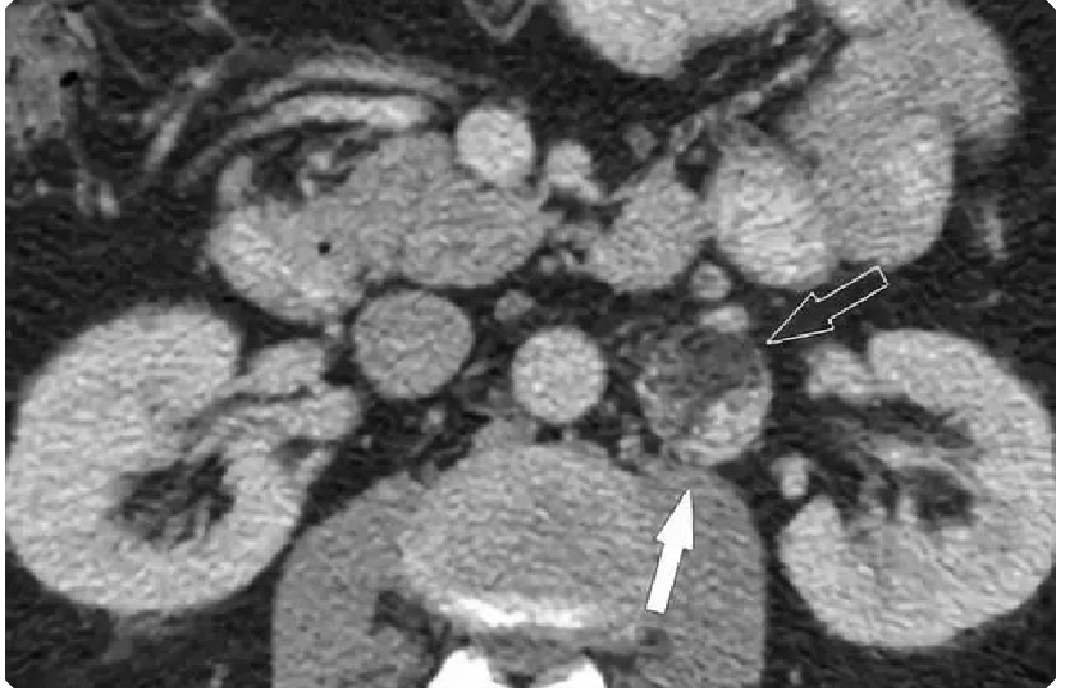

0a5fb18a3933294f8c258284440d05bf.png 病例 8:腹膜后(血管外)平滑肌肉瘤  46岁女性 腹膜后肿物不均质强化,病灶与前方下腔静脉、上方肾上腺及下方肾脏分界清晰,病灶侵犯右侧腰大肌。瘤内少量出血,不均质强化,弥散受限。大体病理显示瘤内出血、坏死;镜下:具有有丝分裂和核异型的梭形细胞。

0a6556b925dbc726a8c295b13d4e5389.png 病例 9:腹膜后(血管外)平滑肌肉瘤  64岁女性右侧腹膜后巨大软组织肿块,不均质强化侵犯肝脏(黑箭)及右肾(白箭)。大体病理显示肿瘤侵犯右肾,瘤内出血、坏死(*)。